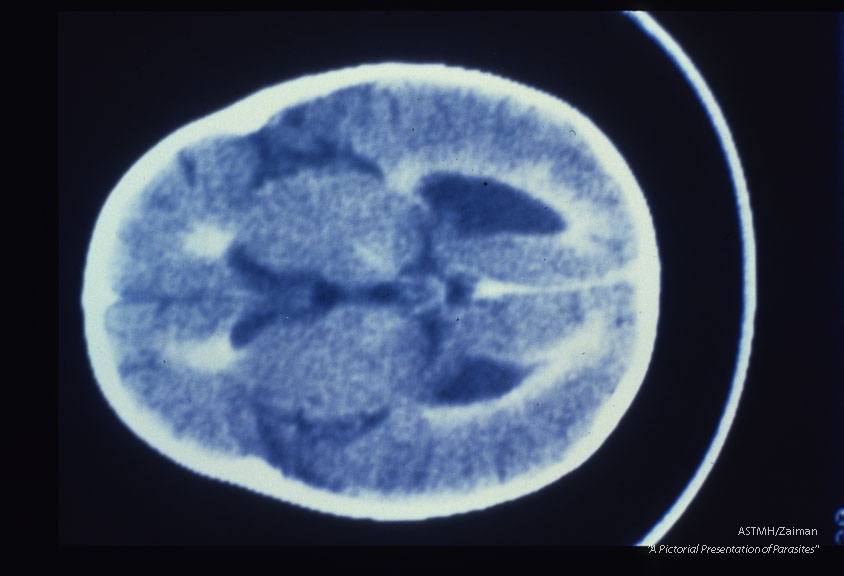

Samecase. Contrast enhanced CT brain scans show ventricular dilatation, periventricular enhance­ment and enlargement of cortical sulci.

Description: Samecase. Contrast enhanced CT brain scans show ventricular dilatation, periventricular enhance­ment and enlargement of cortical sulci.